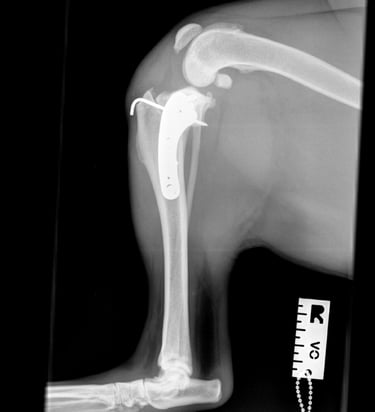

Orthogonal radiographs revealed findings consistent with cranial cruciate ligament disease. The lateral view of the affected limb (Fig. 2) shows joint effusion along with degenerative changes suggestive of osteoarthritis affecting the distal pole of the patella, proximal trochlear groove, and fabellae. The contralateral (left) stifle (Fig. 1) appears normal and serves as a reference. A cranial drawer test was performed under sedation and yielded a positive result.

Fig. 1